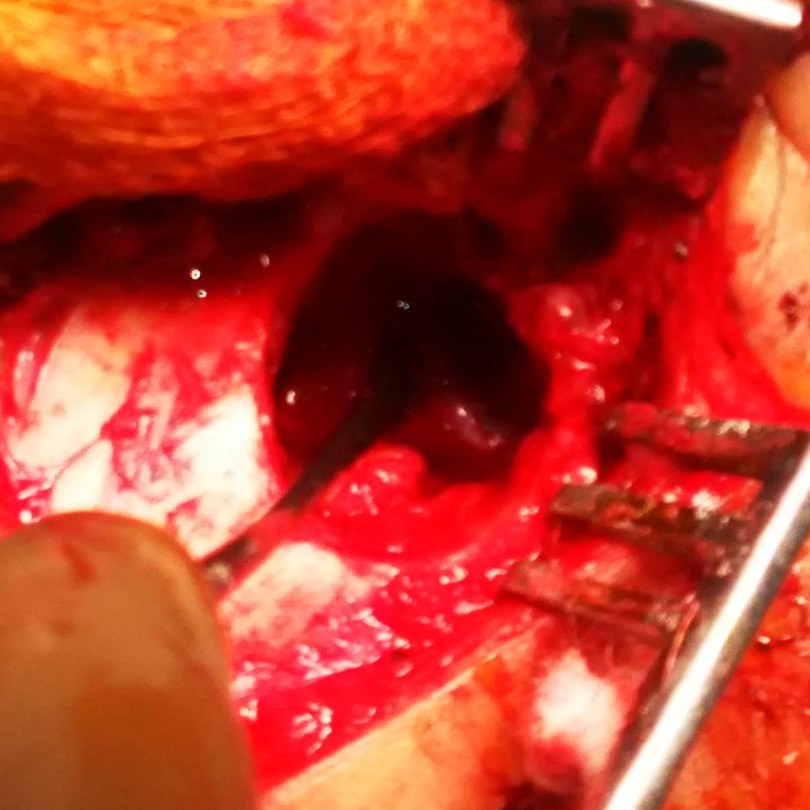

Ear Surgery